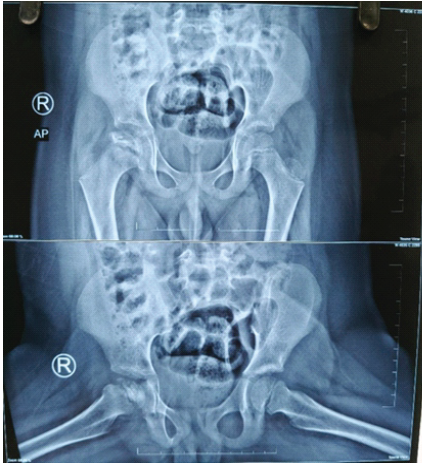

Hip disorders in the paediatric population (patients <16 years) represent a varied collection of conditions ranging from traumatic, developmental, infectious, neoplastic, and metabolic causes [1]. These pathologies, if not promptly diagnosed and treated, frequently result in long-term morbidity, including permanent deformities, chronic pain, gait abnormalities, and compromised quality of life in adulthood [1,2]. The unique developmental anatomy of the pediatric hip, characterized by the presence of a vulnerable physeal plate and changing vascular patterns, contributes to its susceptibility to specific age-related diseases [3]. Common non-traumatic paediatric hip disorders include developmental dysplasia of the hip (DDH) (Fig. 1), Legg-Calvé-Perthes disease (Perthes’) (Fig. 2 and 3), slipped capital femoral epiphysis (SCFE) (Fig. 4), and infective conditions such as septic arthritis (Fig. 5) and tubercular arthritis [3].

Figure 2: Radiographic image of Perthes disease showing loss of sphericity of the femoral head with cystic changes.